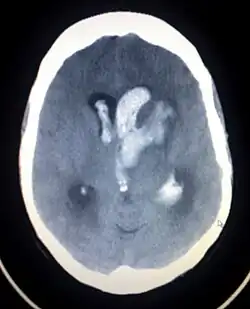

| Axiali CT scan of a spontaneous intracranial hemorrhage | |

A non-contrast CT scan (computed tomography) of the brain is commonly used as the initial imaging modality in suspected cases of intracranial hemorrhage. CT is preferred in emergency settings due to its speed, availability, and high sensitivity for detecting acute brain injuries, enabling rapid triage and surgical decision-making. Examples of brain diseases that require urgent intervention are: large-volume hemorrhage, brain herniation, and cerebral infarction. Additional advantages of CT imaging include its effectiveness in detecting bony fractures, vascular injuries, and cerebrospinal fluid (CSF) leaks.